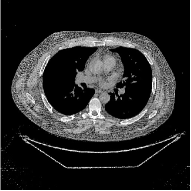

This section compares the reconstruction quality and runtime among the proposed MBIR method, PWLS-ST-, and other three MBIR methods, PWLS-EP, PWLS-DL, and PWLS-ST-. Table I shows that, for both 2D and 3D sparse-view CT reconstructions of the XCAT phantom, the proposed PWLS-ST- model outperforms PWLS-EP and PWLS-ST- in terms of RMSE. In addition, PWLS-ST- using a square transform (of size ) achieves lower RMSE than PWLS-DL using an overcomplete dictionary (of size ) for 2D sparse-view reconstructions. Fig. 3(a) and Fig. 4 show the reconstructed images for 2D and 3D phantom experiments, with different reconstruction models and different number of views. (See the corresponding error maps in the supplement.) The proposed PWLS-ST- consistently gives more accurate image reconstructions compared to other MBIR methods. Specifically, PWLS-ST- has smaller errors in the heart region (see zoom-ins in Fig. 3(a)) of 2D reconstructions than PWLS-DL and PWLS-ST-. In addition, compared to PWLS-ST-, PWLS-DL and PWLS-ST- have some ringing artifacts around the edges with high transition, e.g., edges between air and soft tissues. (See a comparison of profiles of PWLS-ST- and PWLS-ST- in the supplement.) In particular, PWLS-ST- and PWLS-DL give more visible ringing artifacts for 2D reconstruction from fewer views, and PWLS-ST- has these ringing artifacts for 3D reconstructions regardless of the number of views (see zoom-ins in Fig. 4). Table II reports runtimes of different MBIR methods in reconstructing the -views XCAT phantom scan. (FBPConvNet is a non-MBIR method and its runtime for processing a image is approximately one second with a TITAN Xp GPU.) While providing better reconstruction quality, the proposed Algorithm 1 of PWLS-ST- has shorter runtime compared to the algorithms of PWLS-DL and PWLS-ST- in Section III-A. Similar to the PWLS-EP algorithm, the reconstruction time of the PWLS-DL, PWLS-ST-, and PWLS-ST- algorithms can be further reduced by using ordered subsets [51].

| (b) 3D axial cone-beam CT experiments |